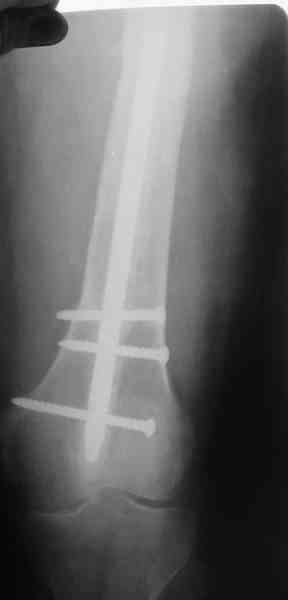

В настоящее время наш пациент ( см. http://weborto.net/forum/1177351385/) ходит с одним костылем. У него периодически открывается свищ на задне-наружной поверхности бедра с умеренным серозно-гнойным отделяемым. Температура тела и анализы нормальные. На рентгенограммах имеются признаки консолидации ложного сустава.

Иллюстрации:

1, 2, 3, 4 - рентгенограммы бедра от 8 августа этого года (через четыре месяца после операции);